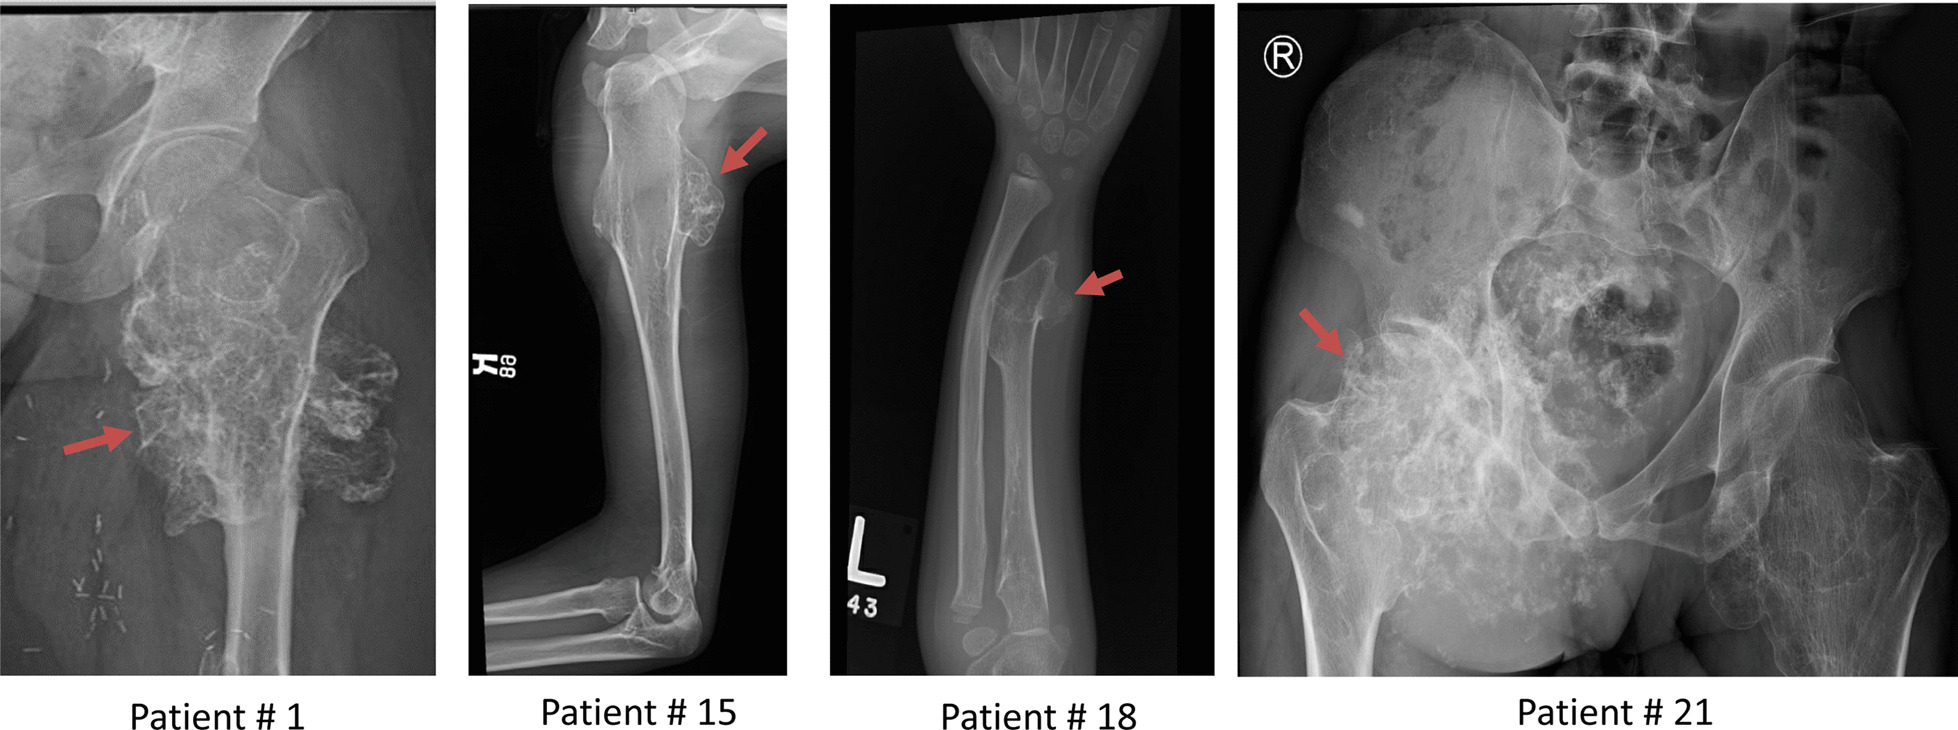

Fig. 1.

Radiology of patients with osteochondromas. Patient#1 has an osteochondroma at left hip joint; Patient #15 has an osteochondroma at right proximal humerus; Patient#18 has an osteochondroma at left distal radius; and Patient # 21 has a right pelvic osteochondroma with malignant transformation. Osteochondroma is indicated by an arrow